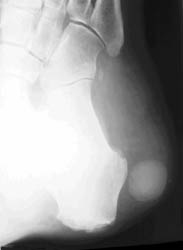

64-year-old male with a painless soft tissue mass in the lateral aspect of the right heel. Plain radiograph demonstrates a densely calcified mass in this region. MR demonstrates this mass to be isointense on T1 and hyperintense on T2W images, with a central area of hypointense calcification.